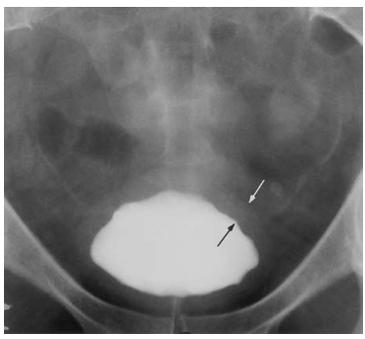

neurogenic bladder